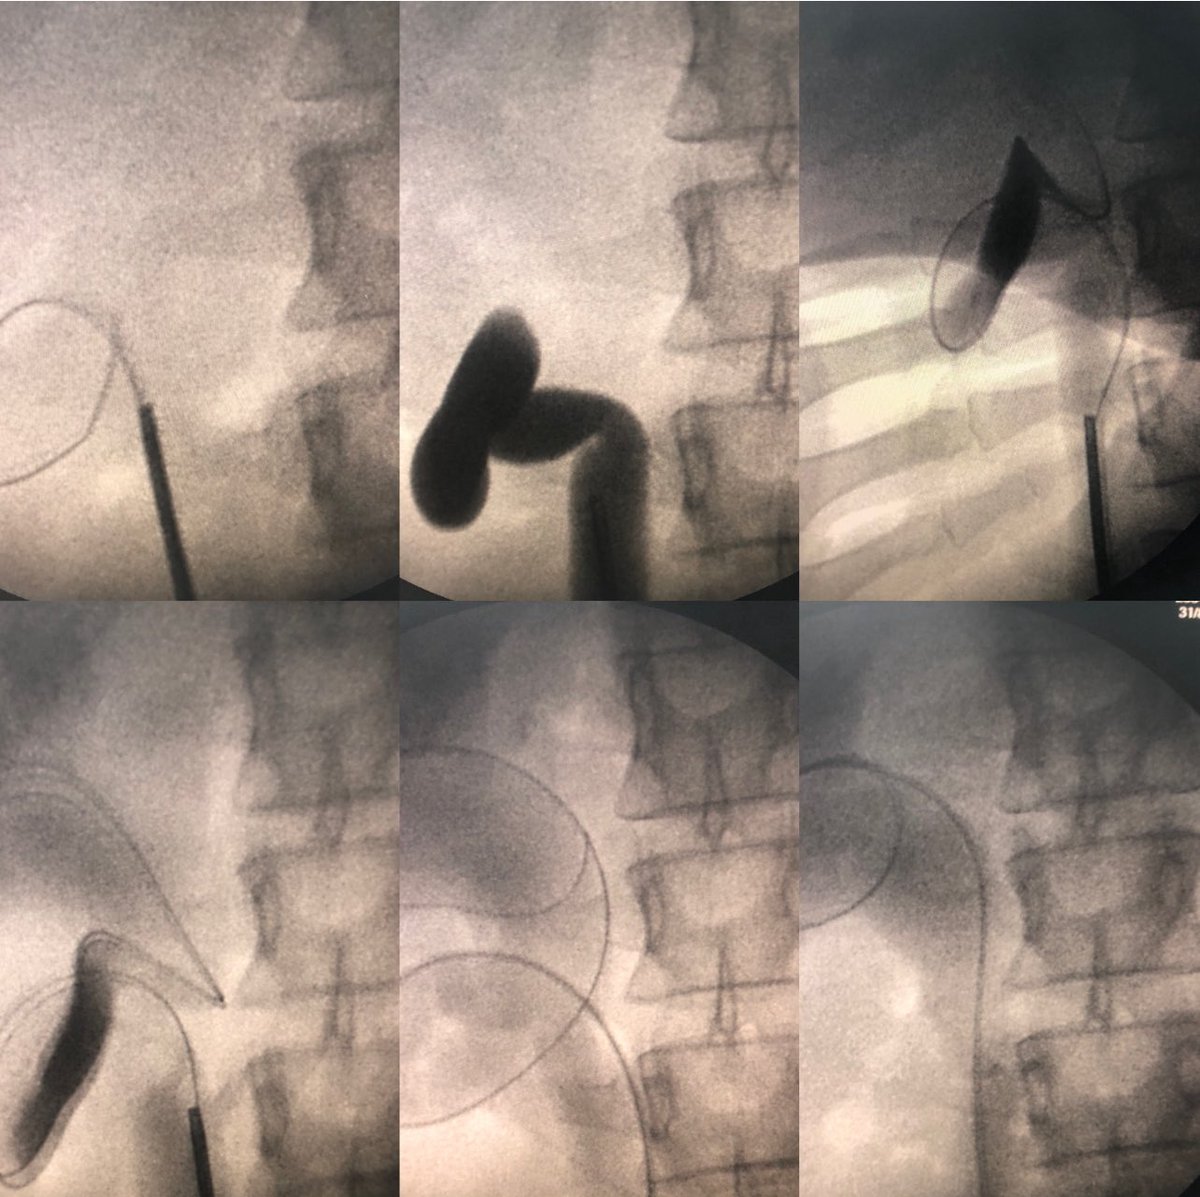

Pushing frontiers of RIRS. Follow up 2 months after RIRS of 3 cm renal pelvic stone in malrotated kidney. Patient refused PCNL. Stenting followed by single session RIRS with FANS.

3

1

34

When your fellow call for guide wire does not go. The rule is ((False passage is medial and lumen is lateral)) Surgeon should go laterally on the opposite side to go easily to ureteric lumen

2

5

68